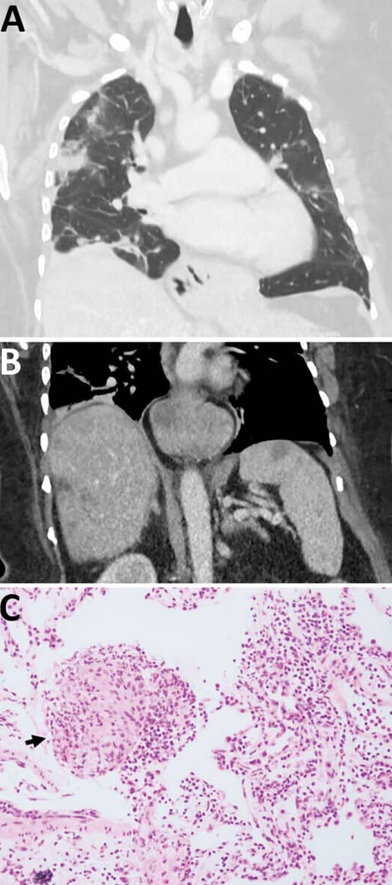

CT skeniranje je otkrilo multifokalne plućne opacnosti s okolnim promjenama tipa mat stakla, nalaz koji Medical News Today definiše kao povećanu gustoću plućnog tkiva koja može ukazivati na upalu ili infekciju. Skeniranje je također pokazalo lezije na jetri i slezeni. Bronhoalveolarna lavaža je pokazala 30 posto eozinofila bez detektabilnih patogena.

Tokom tri mjeseca 2022. godine, pacijentkinja je razvila zaboravnost i pogoršanje depresije dok je nastavila imunosupresivnu terapiju. Magnetna rezonanca mozga pokazala je leziju desnog frontalnog režnja veličine 13 × 10 mm sa perifernim pojačanjem.

U junu 2022. godine, hirurzi su izvršili otvorenu biopsiju. U leziji su uočili strukturu nalik niti i uklonili živog, pokretnog helminta dužine 80 mm i promjera 1 mm. Histopatologija tkiva pokazala je benignu organizirajuću inflamatornu šupljinu s izraženom eozinofilijom.